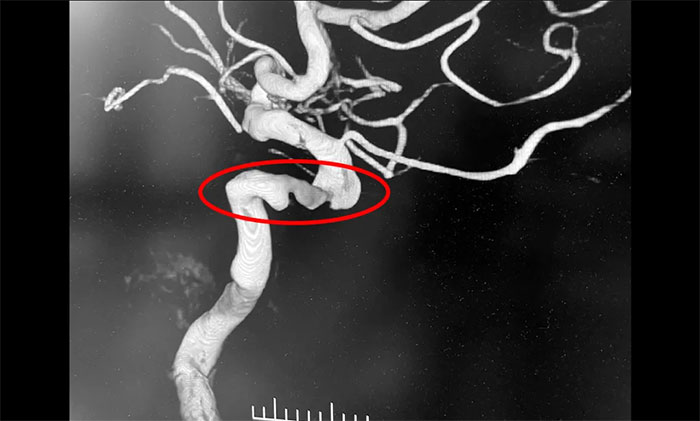

入院后,脑血管造影检查确诊:左颈内动脉海绵窦段、床突段多发动脉瘤,同时左颈内动脉起始段重度狭窄,眼动脉段狭窄,左大脑中动脉M1段闭塞。席刚明教授指出,从治疗的原则上这两种疾病是相互排斥的,血管狭窄的治疗需要进行单抗甚至双抗的一级卒中预防,也就是抗血小板治疗;而动脉瘤的治疗不能进行抗血小板治疗,因为一旦动脉瘤破裂,之前的抗血小板治疗会起到相反的作用,造成出血增加,所以治疗便成了一个“复杂”而又“棘手”的问题。

患者病情表现为缺血性脑血管病,由于同时存在多支脑血管狭窄,而随着年龄的增加,动脉粥样硬化导致的血管狭窄也必然逐渐加重,因此抗血小板治疗势在必行,同时颈内动脉已经出现了重度狭窄近闭塞,因此必须“架桥”,让血流重新供应大脑半球;但是复杂的是,左颈内动脉海绵窦段、床突段多发动脉瘤瘤体角度刁钻,形态不规则,随时都有可能破裂出血,危及患者的生命安全,这个雷也必须得“拆”。神经内科4A病区主任席刚明教授、神经内科4A病区副主任王贵平博士会诊后决定,通过一次介入手术,解决脑血管狭窄的同时处理动脉瘤,将“复杂”的病情“简单”化,一次性解决两个问题,同时避免分期手术带来的一系列创伤。

▲ 颈动脉狭窄合并左颈内动脉海绵窦段、床突段多发动脉瘤